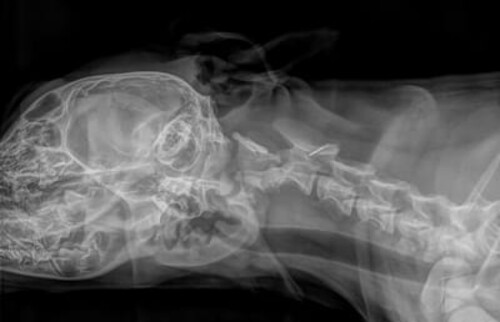

Röntgenaufnahme einer Halswirbelfraktur.

Diagnostische Maßnahmen: Zunächst wurden Röntgenbilder unter Sedation angefertigt, um die Halswirbelsäule zu beurteilen. Aufgrund der Ergebnisse (Verdacht auf Wirbelfraktur c2 inklusive Subluxation) wurde eine CT-Untersuchung empfohlen, um die genaue Fraktur- und Subluxationslage zu klären.

Abb. 1: Verdacht auf eine Fraktur des Wirbelkörpers C2 und eine Subluxation von C2 nach dorsal im Röntgen